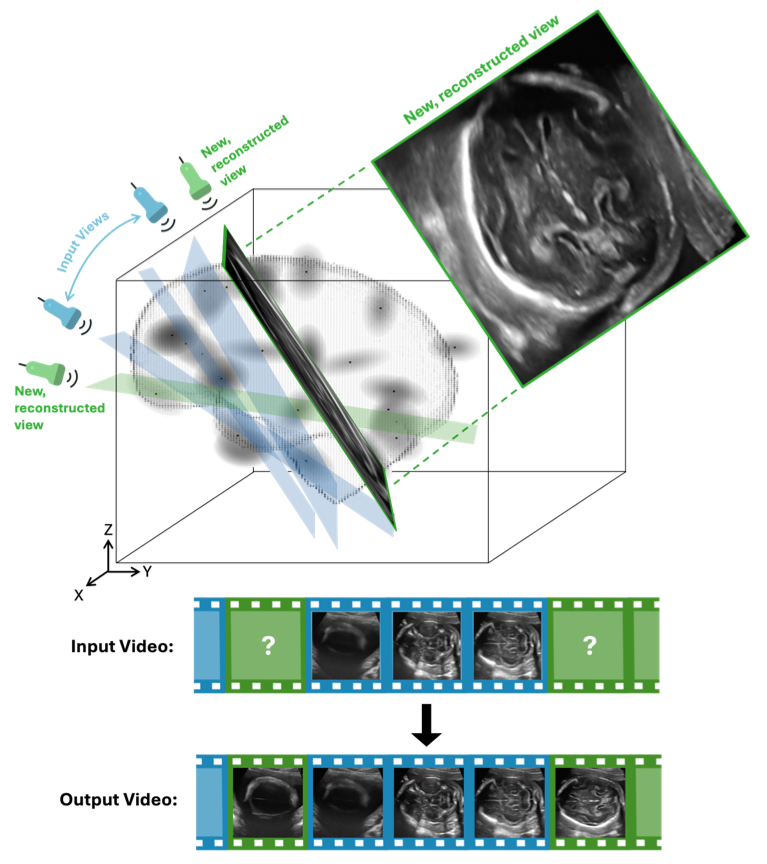

RapidVol: Rapid Reconstruction of 3D Ultrasound Volumes from Sensorless 2D Scans

2025 IEEE 22nd International Symposium on Biomedical Imaging (ISBI)

·

14 Apr 2025

·

doi:10.1109/ISBI60581.2025.10980994